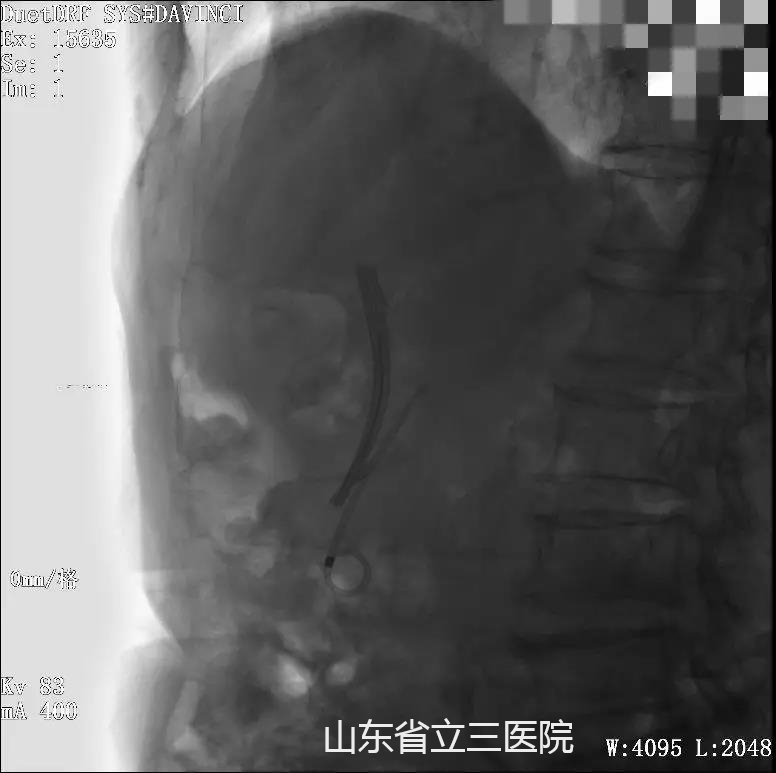

在兩次光動(dòng)力治療后放置支架